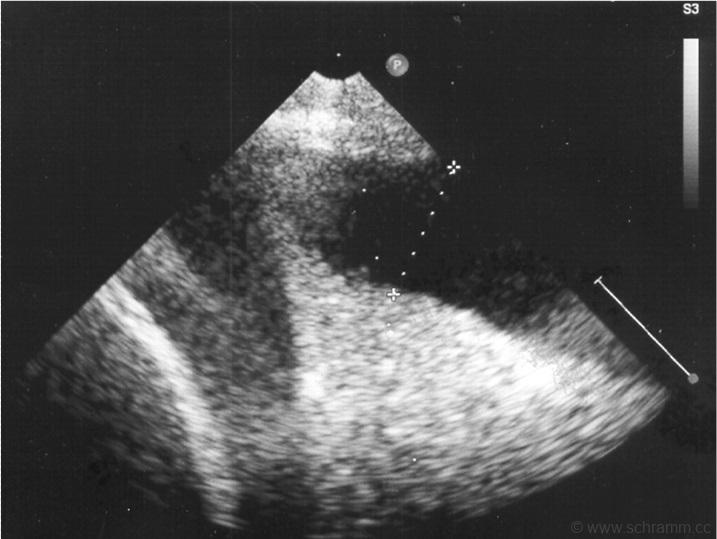

Ultraschallbild des Thorax eines Erwachsenen:

Zeigt einen Pleuraerguss, denn bei einem gesunden erwachsenen Menschen sind die Pleurahöhlen mit jeweils maximal etwa 5-10 ml Flüssigkeit gefüllt.

Es befindet sich Flüssigkeit zwischen der Pleura parietalis und der Pleura visveralis.

Dies ist ein Normalbefund.

Die Ursache dafür könnte eine Hypalbuminämie (mit der Folge eines erniedrigten onkotischen Drucks) sein, etwa bei einem nephrotischen Syndrom.

Die Ursache könnte ein Transsudat als Folge einer Herzinsuffizienz sein.

Die Ursache könnte entzündlich-infektiös sein, die Flüssigkeit wäre demnach ein Exsudat (Pleuritis exsudativa).

Bei größeren Pleuraergüssen (über circa 1 Liter beim erwachsenen Menschen) besteht die Therapie i.d.R. in einer Entlastung durch Entleerung des Pleuraraums mittels Pleurapunktion.